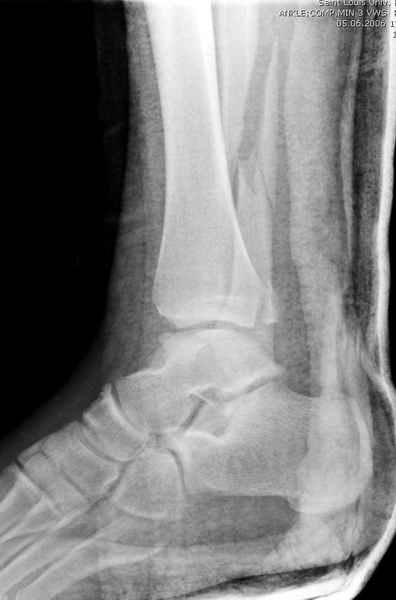

>На сделанных у нас снимках видно, что не все благополучно...

Неравномерность суставной щели может быть связана с разрывом глубокой порции дельтовидной связки и ротацией м/берцовой кости за счет поврежденных структур синдесмоза(репозиция ее на уровне перелома как-будто удовлетворительная).

По моему мнению,ассиметрия суставной щели обусловлена импрессией медиальной части суставной поверхности б/б кости. Да, позиционный винт здесь не лишен, но через 4 недели целесообразность его проведения сомнительна, брейс, ограничение осевой нагрузки достаточно.Есть еще деонтологические аспекты повторной операции, не все так плохо выполнено предыдущим доктором!

Импрессия медиальной части суставной поверхности бывает при супинационном механизме перелома лодыжек (тип А по классификации АО). Здесь механизм пронациия+наружная ротация (тип С, синдесмоз и межкостная мебрана повреждены),

перелом медиальной лодыжки отрывной, при этом в 20-30% бывает повреждение дельтовидной связки.

Клиновидность щели сустава следствие повреждения дельты, невосстановления длины малоберцовой или (хотел сказать "установки в гипсе", но оного, вроде,

нет)? Устранить бы причину. А равно как и тенденцию" к наружному подвывиху. Чрескостный остеосинтез - метод выбора.

Мое мнение, что никакой ротации малоберцовой кости здесь нет и синдесмоз тоже впорядке. Все дело в некачественно репозиции медиального мыщелка. Скорее всего его или немного ротировали при операции или сместили латерально. Более склонен ко второму варианту.

Конечно, компьютерный томограф более информативный метод, но с помощью недорогого обычного стандартного в нейтральном положении стопы: прямого, бокового и косой (ankle mortise) ренгенологического метода можно получить полную информацию о повреждении голеностопного сустава, а сравнительный снимок с другой стороны подтвердить наличие повреждения.

При реконструкции голеностопа, о важности восстановления длины малоберцовой для профилактики пост травматического артроза разбирали в предыдущих дискуссиях. Нарушенную биомеханику голеностопа без восстановления длины малоберцовой, не восстановить только швом медиальной связки.

Расширенная медиальная щель более чем на 4 мм и укорочение малоберцовой более чем 2 мм, а перелом заднего края большеберцовой смещения более 2мм с вовлечением 30% поверхности сустава, считается отходом от нормы голеностопного сустава, и подлежит к оперативному вмещательству.